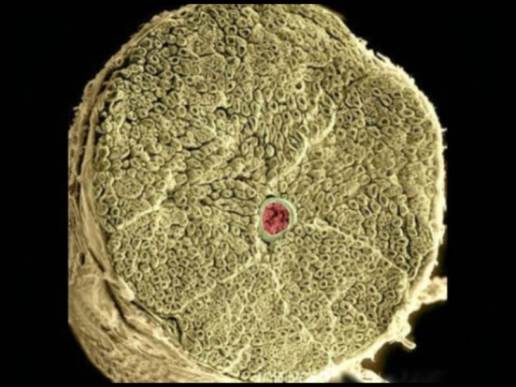

Porém, em nível microscópico, não apresenta divisões entre as camadas. As estruturas de colágenos se comportam em forma caótica, como poliedros, formando microváculos onde a estrutura se organiza em um padrão não-newtoniano (Guimberteau, 2013). Nesse nível o sistema obedece aos princípios das leis quânticas (Bordoni, 2017). Assim, é imperativo desenvolver-se ferramentas de avaliação e tratamento desse tecido em um padrão de acordo com a sua anatomia e característica.